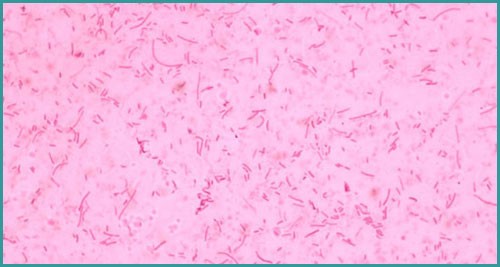

- Tác nhân: Haemophilus parasuis, một loại vi khuẩn Gram âm, hình cầu – que ngắn.

Vi khuẩn Haemophilus parasuis gây bênh Glasser. Nguồn: Sưu tầm